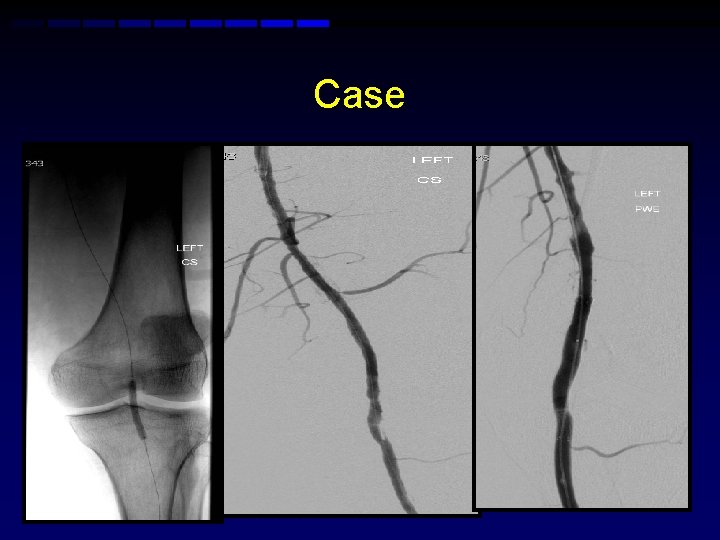

Case • 50 yr old with HTN, hypercholesterolemia and smoker presents with left calf claudication • ABI 0. 72 advised medical therapy • No relief of caludication • Angiogram performed via right CFA

Case • Right retrograde femoral access • Attempt to cross the left popliteal • Subintimal pass • ? Pioneer

Left antegrade puncture

Case